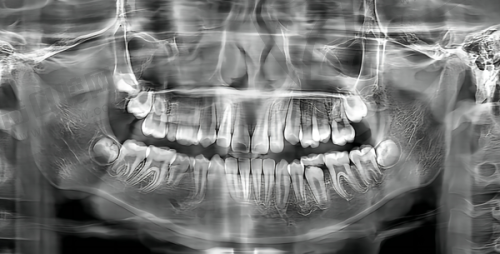

特别多人都关心矫正牙齿的至佳年龄段,其实啊,牙齿矫正有几个关键的时期,在这些时期进行矫正往往能达到更好的成效。一般来说,青少年时期是矫正牙齿的黄金阶段,这个时候人体的生长发育还在进行,牙齿和颌骨都比较容易调整,矫正起来相对轻松,而且能取得特别不错的成效。不仅如此,现在还有众多真人实例可供参考,大家可以从中感受到矫正前后的巨大变化。接下来,我们就详细了解一下不同阶段矫正牙齿的特点和优势。